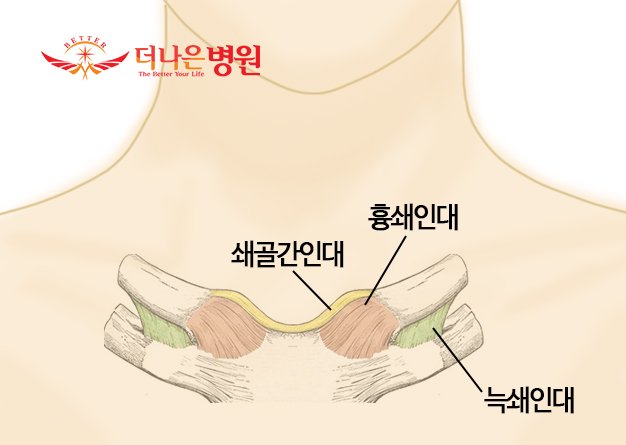

흉쇄관절(SC joint)은 쇄골의 내측단, 흉골의 쇄골면, 그리고 첫 번째 늑연골의 상연으로 구성된 복잡한 관절입니다. 이 관절은 주축골격과 부속골격을 연결하는 상지의 기저부 관절입니다. 이런 독특한 기능적 특징을 가진 흉쇄관절은 복잡한 안장 형태의 관절면을 갖고 있습니다. 쇄골의 내측단은 세로 직경이 볼록하고 가로 직경이 오목한 모양이고, 쇄골의 내측단과는 상반된 형태로 갖고 있는 흉골의 쇄골단은 세로 직경이 약간 오목하고 가로 직경이 약간 볼록하게 생겼습니다. 이는 주변 인대 및 관절원판과 함께 흉쇄관절이 경사진 흉골의 관절면 위에 에 쇄골이 얹혀져 있는 불안정성을 완화시켜 움직임을 안정적으로 일으키게 도와주는 역할을 합니다.

흉쇄관절의 주위에는 다양한 결합조직 및 근육에 의해 안정성을 가지게 됩니다. 전흉쇄인대와 후흉쇄인대에 의해 보강된 관절낭에 둘러 싸여 있고 이러한 관절낭의 안쪽면에는 윤활막이 위치해 있습니다. 관절낭 외에도, 전방으로는 흉쇄유돌근의 흉골두 그리고 후방으로는 흉골갑상근과 흉골설골근에 의해 흉쇄관절은 안정되게 됩니다. 또한 경절흔에 걸쳐 뻗어 있는 쇄골간인대는 오른쪽 쇄골과 왼족 쇄골의 내측단들을 서로 연결시켜 주고, 늑쇄인대는 첫 번째 늑골의 연골에서부터 쇄골의 하면에 있는 늑골조면까지 뻗어있으며 앞쪽 다발은 상외측 방향으로 주행하고, 뒤쪽 다발은 상내측 방향으로 주행하는 서로에 대해 수직으로 주행하는 두 개의 섬유 다발을 갖지고 있고, 흉쇄관절을 단단히 고정시키며 쇄골의 하방 움직임을 제외한 모든 쇄골의 과도한 운동을 제한하게 됩니다.

흉쇄관절에 있는 관절원판은 관절을 내측강과 외측강으로 분리시킵니다. 편평한 섬유연골인 원판은 아래쪽으로는 쇄골면의 외측 가장자리 근처에 부착되고 위쪽으로는 쇄골두와 쇄골간인대에 부착되고, 원판의 나머지 바깥쪽 가장자리는 관절낭의 안쪽면에 부착되게 됩니다. 원판은 관절면의 접촉영역을 증가시켜 관절내부에 대한 충격 흡수의 기능을 수행하게 됩니다. 이러한 충격 흡수의 기전에 의해 흉쇄관절에는 퇴행성관절염이 거의 나타나지 않습니다. 앞서 말했듯 흉쇄관절에서의 안정성은 이 관절을 에워싸고 있는 관절주위 결합조직들에 의해 이루어집니다. 이러한 결합조직의 단단한 고정은 쇄골을 통해 내측방향으로 전달된 큰 힘에 의해 흉쇄관절의 탈구 대신 쇄골 간부의 골절을 유발하게 됩니다. 쇄골골절은 30세 이하의 남성에서는 아주 흔히 일어날 수 있습니다. 이러한 골절의 대부분은 접촉이 많은 스포츠나 교통사고에 의해 유발되게 됩니다.